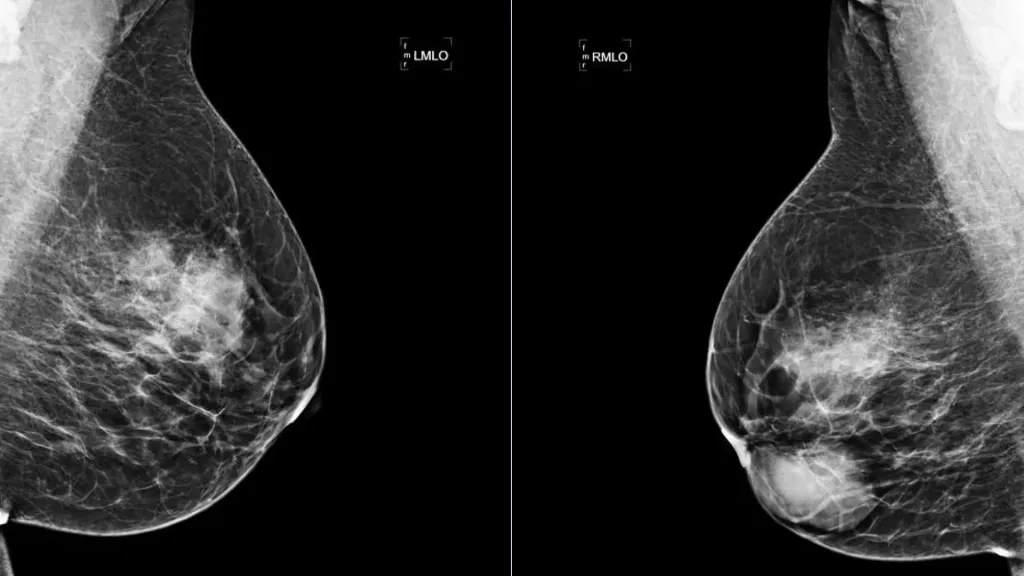

രോഗം എങ്ങനെ നേരത്തെ കണ്ടുപിടിക്കാം?

ചില അരുതായ്കകൾ

സ്വയം പരിശോധന വളരെ അത്യാവശ്യമാണെങ്കിലും സ്വയം ചെയ്യാൻ പാടില്ലാത്ത ചില കാര്യങ്ങളുണ്ട്. അത്, സ്വയം രോഗനിർണയ പരിശോധനകൾക്ക് ഇറങ്ങിത്തിരിക്കരുത് എന്നതാണ്. പ്രത്യേകിച്ചും മാമ്മോഗ്രാം പോലെ അണുവികരണസാധ്യതയുള്ള ടെസ്റ്റുകൾ ഒരിക്കലും സ്വയം ആവശ്യപ്പെട്ടു ചെയ്യാൻ പാടില്ല. ഈ പരിശോധനകൾ ചെയ്യാവുന്നതും, ചെയ്യാൻ പാടില്ലാത്തതുമായ അവസരങ്ങൾ ഒരു ഡോക്ടർക്കു മാത്രമേ തീരുമാനിക്കാൻ കഴിയൂ. താരതമ്യേന ദോഷം കുറവുള്ള അൾട്രാ സൗണ്ട് സ്കാൻ പരിശോധന പോലും ഡോക്ടറുടെ നിർദേശപ്രകാരം മാത്രമേ ചെയ്യാൻ പാടുള്ളു. അത് പോലെ തന്നെ സംശയമുള്ള സാഹചര്യങ്ങളിൽ ഒറ്റമൂലി ചികിത്സകൾ, ഫലപ്രാപ്തി അറിയാത്ത വിവിധ സമ്പ്രദായങ്ങളിൽ ചികിത്സകൾ, സമൂഹ മാധ്യമങ്ങളും മറ്റും ചർച്ച ചെയ്യുന്ന ശാസ്ത്രീയ അടിത്തറയില്ലാത്ത ചികിത്സകൾ തുടങ്ങിയവ തേടിപ്പോകരുത്.

• നാൽപതു വയസ്സ് കഴിഞ്ഞാൽ, കുടുംബം പൂർത്തിയായിക്കഴിഞ്ഞാൽ, ആവശ്യമുള്ള സമയത്ത് മാമ്മോഗ്രാം, കാ​ലേക്കൂട്ടിയുള്ള പരിശോധനകൾ, രോഗനിർണയം, ചികിത്സ എന്നിവ മറക്കാതിരിക്കുക.